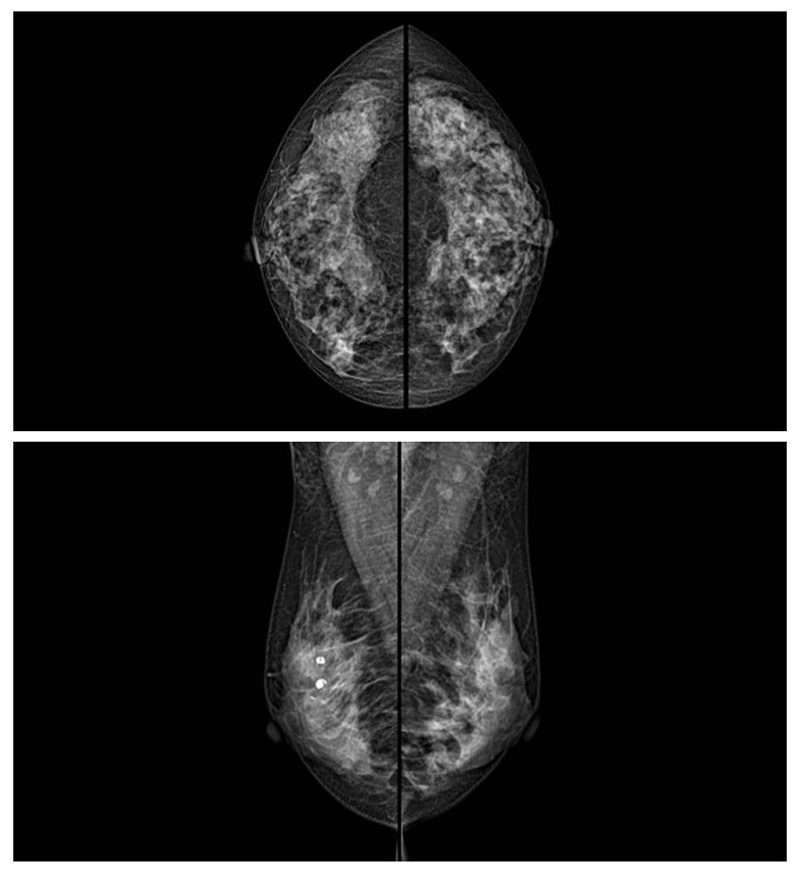

乳腺癌的發(fā)生率越來越高,已經(jīng)是我們國家的癌癥之一已成為女性健康“頭號殺手”。乳腺DR可提高乳腺癌早期檢出率并精準定位。發(fā)現(xiàn)和診斷早期乳腺癌最有效的方法之一,明顯利大于弊女性都要重視乳腺的檢查。輻射很小最簡便、最可靠、無創(chuàng)性檢查手段,做一次乳腺DR的劑量相當于7周的正常生活。尤其是對于40歲以上的女性尤為重要,那么乳腺DR是怎么進行檢查的呢?我們來了解一下,為廣大朋友在檢查前有點心理準備。檢查時候是避開經(jīng)期的前后,月經(jīng)來后的7天左右比較合適。需要脫衣服檢查,根據(jù)拍片的擺位要求,有頭尾位置,內(nèi)外斜位,還有側(cè)位。定點放大壓迫方法可以更細微清晰的檢查出病灶。

對乳房進行按壓,這樣才能得到檢查的好效果,按壓大概60秒左右,做好心理準備不可以過度緊張有點疼痛感覺,這樣不會抖動影響了檢查的效果。減少患者壓迫時間和輻射劑量??蛇_到最高極限分辨率10.1 lp/mm,可實現(xiàn)高清成像,提高微小病變檢出率。可以發(fā)現(xiàn)乳腺增生,各種良惡性腫廇通過三維斷層掃描,提高乳腺微小癌灶的檢出率和早期乳腺疾病特別是乳腺癌的診斷率。通過特殊的支架,加大膠片與物體之間的距離來獲取更多的影像信息。